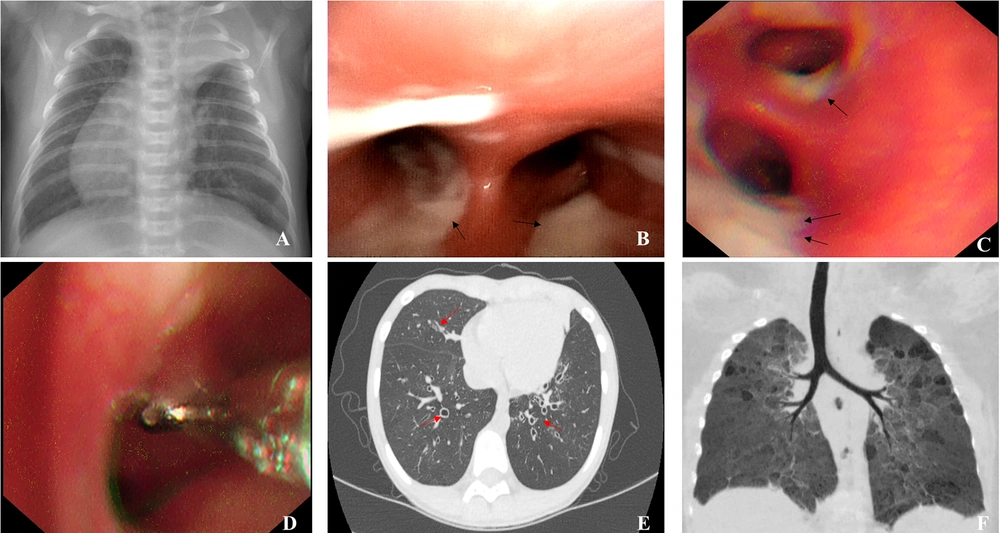

A total of 24 children (14 males, 10 females) were recruited for this study. Due to the small sample size and outcome distribution, comparative and logistic regression analyses were avoided. Instead, the patients’ clinical features were described to explore potential associations. Overall, the mean age of symptom onset was 3.81 ± 3.16 years (range: 0 to 11 years) and the mean age at diagnosis was 2.32 ± 2.28 years (range: 1 month to 10 years). Twenty-two cases (91.67%) exhibited cough and recurrent expectoration of yellowish-brown or green purulent sputa; 10 cases (41.67%) exhibited recurrent wheezing; and 7 cases exhibited signs of malnutrition (29.17%), including 3 cases with severe malnutrition and 4 cases with moderate malnutrition. Other clinical features included electrolyte disorders, rhinitis, sinusitis, otitis media, hearing loss, total visceral inversion (Figure 1A), gastroesophageal reflux, allergic purpura, ichthyosis, premature delivery, anemia, tracheal diverticulum, and severe pneumonia (Table 1).

Representative bronchoscopy and computed tomography (CT) images: A, atelectasis of left upper lobe, right heart, and total visceral inversion (case 4); B, abundant viscous sputum as seen under bronchoscope (case 1); C, abundant thick sputum observed under bronchoscope (case 8); D, bronchial mucosal biopsy (case 8); E, chest CT image showing extensive bronchiectasis (case 3); F, CT reconstruction showing bronchopulmonary dysplasia-induced airway changes (case 16)

Nineteen children (79.17%) underwent bronchoscopy, revealing tracheobronchial intimal inflammation and obstructed airways with abundant secretions (Figure 1B and C). Subsequently, 5 patients underwent bronchial mucosal biopsy (Figure 1D), which revealed an absence of inner and outer dynein arms in 1 patient (case 3). All 24 patients underwent high-resolution computed tomography (HRCT), which revealed bronchiectasis in 14 patients (58.33%; Figure 1E).

4.4. Genetic Testing Results